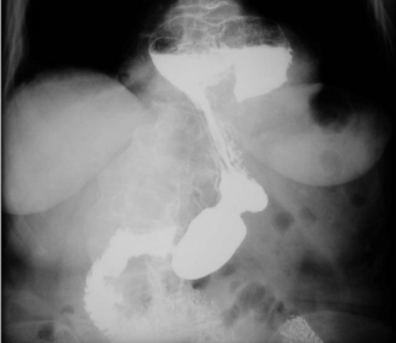

Hiatal hernia refers to protrusion of abdominal contents into the thorax secondary to dilation of esophageal hiatus in diaphragm. There are two types of esophageal hiatal hernia i.e., sliding hiatal hernia and paraesophageal hernia. Sliding hernia is also known as type I hiatal hernia. It is more common than the paraesophageal hiatal hernia. On radiology, it gives a typical ‘hourglass apperacne’. Reference: https://clinicalanatomy.com/mtd1/334-esophageal-hiatus-hernia Image via: https://slideplayer.com/slide/4720524/